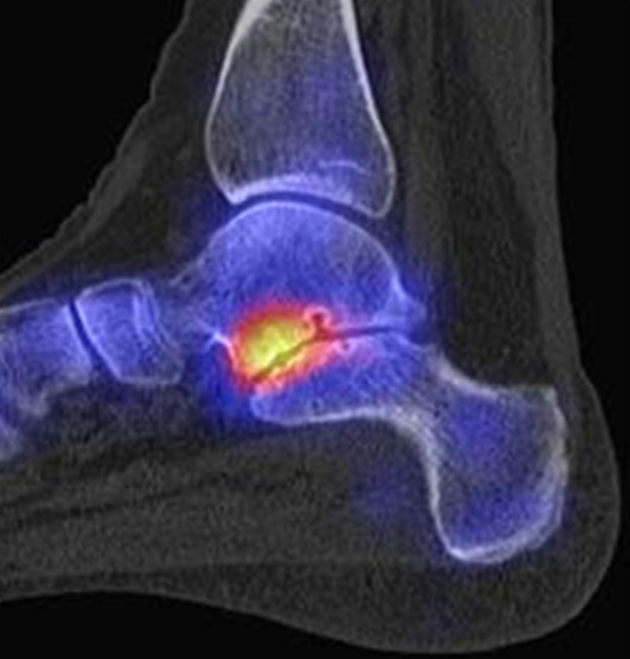

Abbildung 2.3.

Klärung bei Schmerzen im rechten OSG bei OCL an der medialen Talusschulter. Z. n. OSG-Distorsion vor 2 Jahren und Z. n. OSG-Fraktur / Syndesomosenruptur. Ausgedehnte OCL, hier jedoch kein erhöhter Knochenmetabolismus; lediglich Nachweis einer Stressreaktion im Bereich der Synchondrose eines Os trigonum als Schmerzursache.

Zum Lesen der Bildbeschreibung und zur Vollansicht bitte das Bild anklicken. Bild: H. C. Rischke